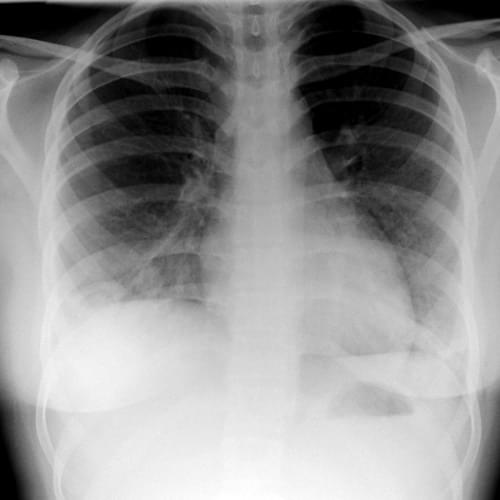

19. A 73-year-old man presents with dyspnoea. A chest x-ray is performed. What is the main finding in the chest x-ray?

Her chest x-ray is shown here:

What is the likely diagnosis?